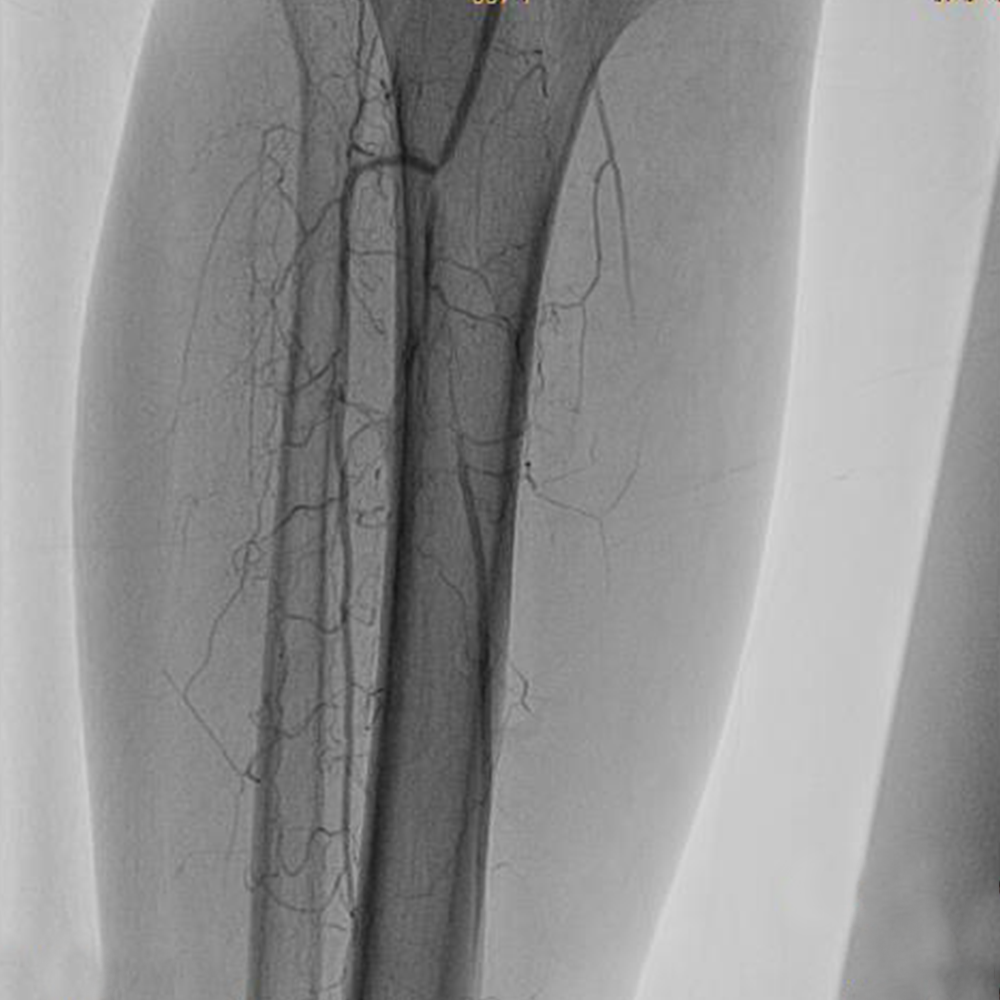

Tibial Artery Occlusion

Endovascular treatment of infrapopliteal lesions has become more common and techniques continue to improve, Vascular Specialists are exploring use of endovascular therapy in more distal arterial territories.

The pedal loop technique, allows for intervention on the distal tibial arteries and the pedal/plantar loop while only using one access site which can improve transcutaneous oxygen tension in the foot at 15 days.  The angiosome concept has gained popularity as an approach to improve limb salvage, whereby the target vessels for revascularization are chosen based on the angiosome in which the wound is located. The limb salvage was 86% when wound angiosomes were directly revascularized versus 69% for indirect revascuarlization.

PREOPERATIVE ASSESSMENT AND PREOPERATIVE IMAGING with Duplex scan of lower limb arterial system,CT angiogram and In most patients, standard arteriography is still the “gold standard. If endoluminal therapy is the case, Endoluminal/Endo Vascular treatment at the time of diagnostic arteriography is  performed.

If open bypass is the plan, then  the focus is to visualize potential target arteries and obtain multiple views, as required, to ascertain that no unexpected inflow disease is present that would require treatment before proceeding with Infra inguinal bypass. Although most claudicants require only femoropopliteal bypass, a high proportion of patients with CLI require tibial or pedal bypass. Patients with CLI generally require intervention, since patients with CLI pose a more complex problem because there is a high anticipated amputation rate without lower extremity arterial reconstruction.

Thus, a patent anterior tibial or posterior tibial artery in direct continuity with the foot and pedal arch would be chosen. The preferred conduit for Bypass surgery is Autogenous Vein graft (Saphenous vein)